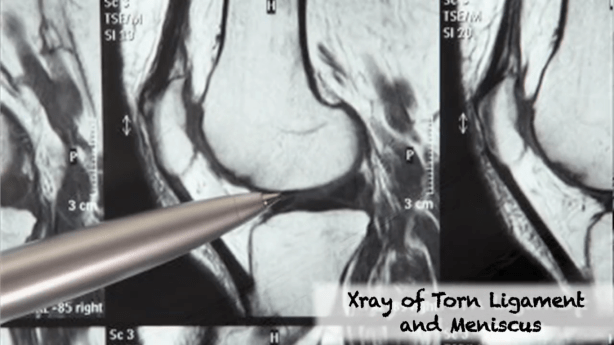

The images for this interview are taken from Stoksies’ stunning film series StRaNGe Beautiful LIFE project. In Episode 5 he talkss of his injury and shows a pretty good account of his recovery back to full fitness!